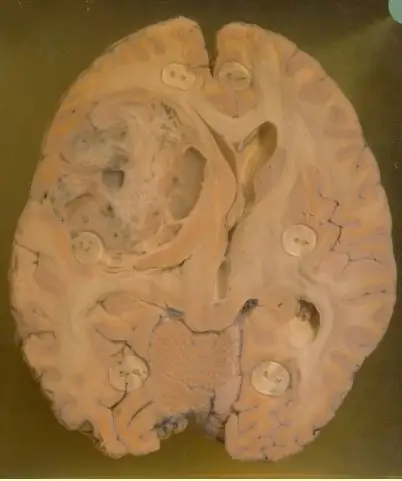

Музей болезней человека содержит более 2 500 образцов (также известных как «горшки»), в которых представлены больные ткани человека, сохраненные в формалине. Образцы получают как из органов, удаленных хирургическим путем, так и из тканей, полученных при вскрытии тех, кто пожертвовал свои тела науке.

Среди множества банок с влажными образцами в музее представлены экспонаты паразитов, таких как солитер и аскариды, почерневшие легкие курильщиков и шахтеров, а также доброкачественная тератома яичника, из которой растут зубы и волосы. Это. Каждая банка представляет определенное заболевание или патологию человека. Режиссер отмечает, что «в каждой банке много страданий». Некоторым образцам более 60 лет, и они стали довольно редкими, например дифтерия, и теперь, к счастью, «незаменимы».”

Музей, который когда-то был открыт только для студентов-медиков и патологоанатомов, теперь открыт для публики в надежде, что он может помочь изменить поведение своих посетителей. «Я полагаю, это реальность, которую люди должны понимать: их образ жизни и их решения имеют последствия, даже если они не замечают их в течение нескольких лет», - сказал директор музея.